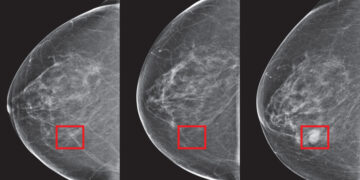

Inteligjenca artificiale parashikon kancerin 5 vite para se ai të zhvillohet

08:56 29/07/2024